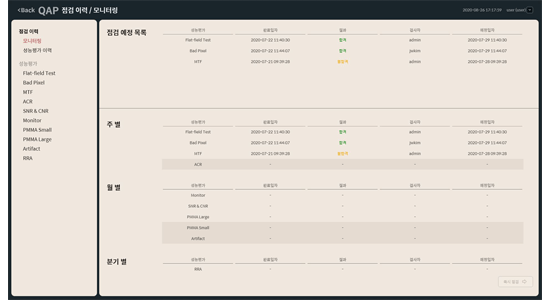

Protocolo de control de calidad global especializado en mamografía

- QAP universal: Admite más de diez protocolos QAP para el mantenimiento de la más alta calidad del sistema y de la imagen.

- Manual digital: Proporciona un manual digital para procedimientos de control de calidad fáciles y rápidos.

- Historial de QAP: Seguimiento del historial de informes QAP para el mantenimiento sistemático.